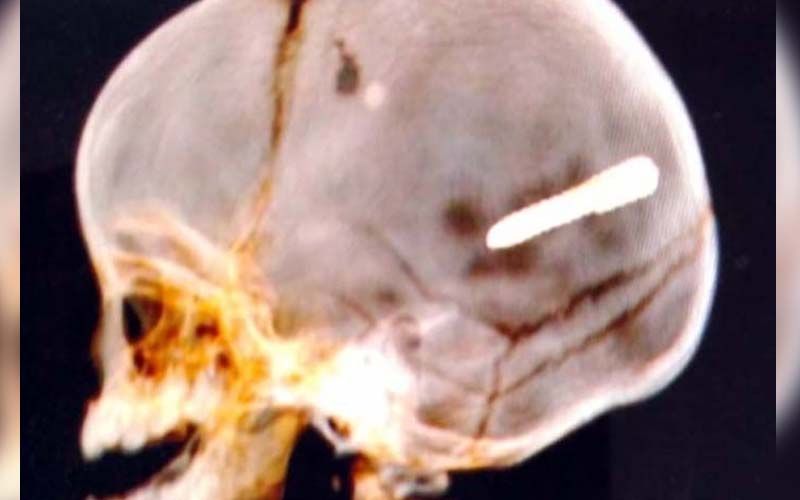

A criança foi socorrida. Uma tomografia computadorizada revelou que o objeto ficou alojado na cabeça do bebê. Segundo a Secretaria Municipal de Saúde, o menino está em estado grave.